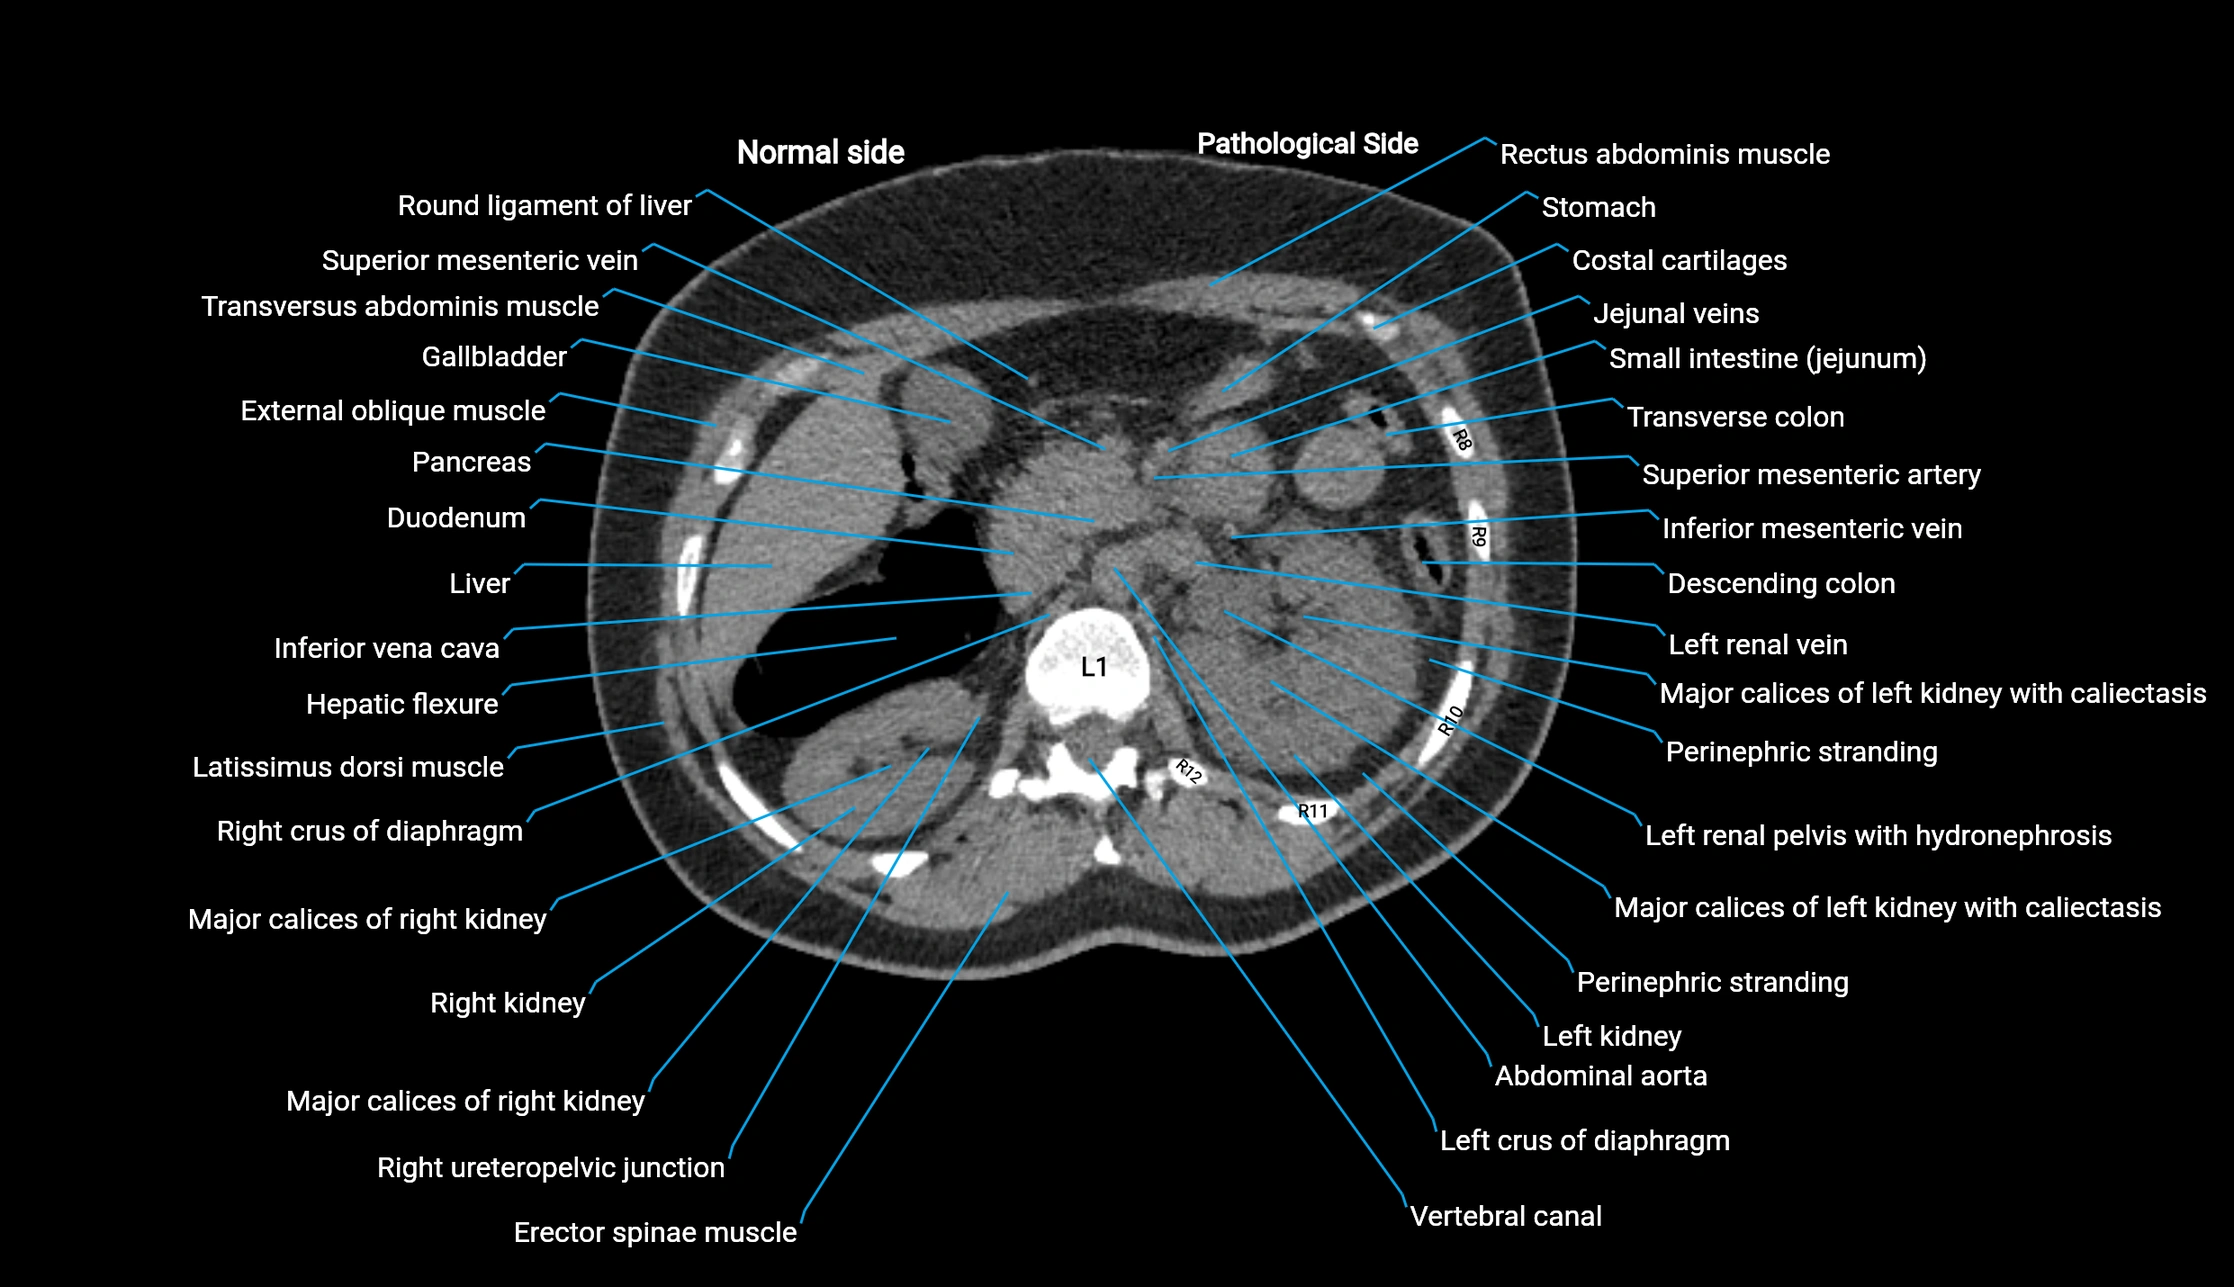

CT image

image